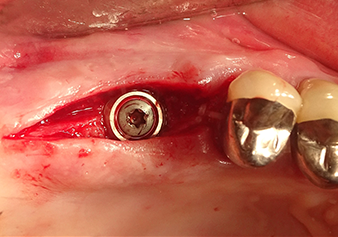

Situazione dopo aver inserito l'impianto

Fig.9: situazione dopo aver inserito l'impianto (lunghezza: 10 mm, piattaforma protesica: 6,5 mm) immediatamente prima della sutura.